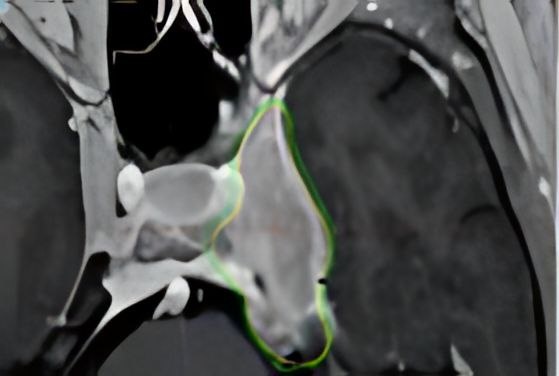

Менингиома головного мозга: когда стоит выбрать радиохирургию

Менингиома — это опухоль, возникающая из клеток твердой мозговой оболочки головного или спинного мозга. В большинстве случаев она доброкачественная (I степень по ВОЗ), но может быть атипической (II степень) или злокачественной/анапластической (III степень). Радиохирургия (стереотаксическая радиохирургия, СРХ) — это неинвазивный метод, использующий высокие дозы облучения для уничтожения опухолевых клеток и достижения контроля опухолевого роста. Она применяется в следующих случаях: 1. Неоперабельные менингиомы до 3,5 см в диаметре 2. Рецидивы или остаточные менингиомы после не радикальной операции Если после резекции осталась опухолевая ткань, СРХ позволяет контролировать ее рост. При рецидивах, когда повторная операция рискованна или не целесообразна. 3. Менингиомы без перифокального отека при отказе пациента от предложенного хирургического лечения Некоторые пациенты выбирают радиохирургию из-за меньшего риска осложнений и отсутствия реабилитационного периода. Контроль роста: 85/95% дл

• Расположение в труднодоступных зонах (кавернозный синус, основание черепа, петрокливальная область).

• Риск повреждения критических структур (ствол мозга, зрительные нервы, крупные сосуды).